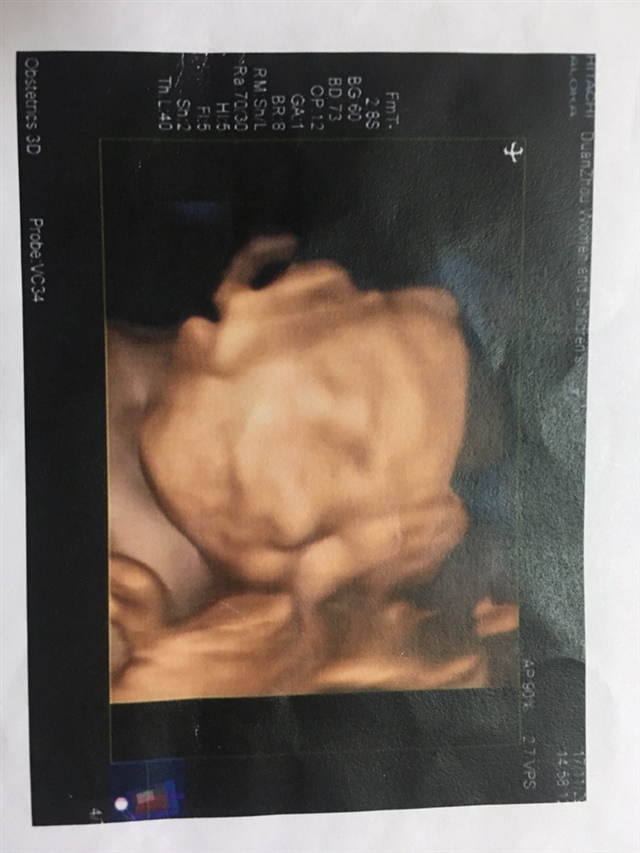

孕14周+5天

孕11周+5天